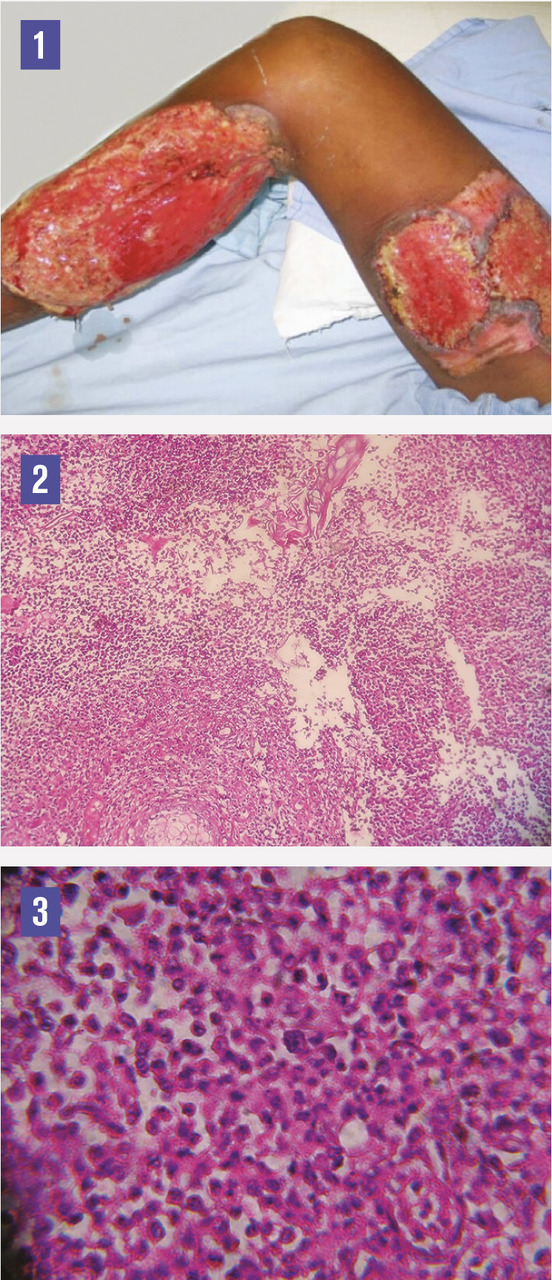

Ce jeune homme de 21 ans avait une ulcération cutanée du mollet droit évoluant dans un contexte fébrile. Une antibiothérapie anti-staphylococcique était prescrite, avec un parage chirurgical et une tentative de couverture par greffe de peau prélevée de la cuisse droite, ce qui a engendré deux ulcérations cutanées étendues hyperalgiques de la jambe et de la cuisse à fond nécrotique bien limitées à bordure violacée surélevée avec un œdème blanc mou du dos du pied et un flessum du genou (fig. 1). Les biopsies montraient un épiderme nécrotique et un infiltrat inflammatoire riche en polynucléaires neutrophiles et lymphoplasmocytes au niveau du derme avec des lésions de vasculite (fig. 2 et 3). Le diagnostic de pyoderma gangrenosum pathergique était retenu et une corticothérapie par voie générale (prednisone) prescrite avec une évolution spectaculaire. Aucune pathologie associée n’a été retrouvée.

Le pyoderma gangrenosum est une dermatose neutrophilique rare, sa forme ulcéreuse est la plus fréquente.1 L’ulcère cutané a un aspect caractéristique : les bords sont réguliers, saillants et circulaires. Ce bourrelet a un aspect inflammatoire rouge violacé et creusé de clapiers purulents. L’ulcération est généralement unique, mais des formes multiples ont été décrites.2 Dans 20 à 30 % des cas, le pyoderma gangrenosum survient à la suite d’un traumatisme ou d’un acte chirurgical (pathergie).3, 4 La corticothérapie par voie générale constitue le traitement de référence.4